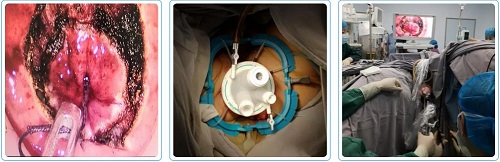

日前,副院长、普外科主任、胃肠外科主任李乐平和东院胃肠外科靖昌庆主任手术团队为一例肿瘤距肛门仅4厘米的超低位直肠癌患者根治切除肿瘤并成功保留了肛门及功能。

在李乐平和靖昌庆教授的带领下,胃肠外科手术团队经过充分的术前准备,成功为患者实施了经肛门路径手术,手术历时3小时,根治性切除直肠肿瘤并保留了肛门和功能,避免了影响生活质量的肠造口,患者顺利恢复,满意出院。

TaTME手术是一种针对超低位直肠癌的微创保肛手术,由于手术入路从传统的经腹部手术转变为经肛门的单孔手术入路,颠覆了传统手术习惯和视野,手术难度大,技术含量高。我院的腹腔镜直肠癌全直肠系膜切除手术(TME)已普及化和规范化,我院胃肠外科每年举办10期的腹腔镜胃肠道肿瘤手术学习班向全国各地医院介绍我们直肠癌的腹腔镜手术经验。但部分超低位的直肠癌仍无法保留肛门,尤其是男性、前列腺肥大、肥胖、直肠系膜肥厚、低位直肠前壁肿瘤、骨盆狭窄、新辅助放疗引起的组织平面不清晰等所谓“困难骨盆”的直肠癌患者,如果采用传统的TME手术,保肛的手术操作十分困难,经常会出现切除肿瘤不彻底造成肿瘤复发。而患者对生活质量和肛门保留的要求也需要一种新的手术技术避开“困难骨盆”对手术造成的不利影响。

TaTME手术的最大优势在于可直视下从直肠腔内精确地离断远端直肠,确保肿瘤足够的远切缘和环周切缘,在保证根治度的前提下提高了保肛率。避免了传统手术方式在狭窄骨盆内离断直肠的“不精确”操作。同时,经肛门这一天然孔道实施手术并做吻合,腹部无切口,患者的创伤更小、疼痛感更低,更加美观且恢复更快。此外,TaTME手术减少了腹腔镜切割闭合器的使用,降低了患者的经济负担,具有良好的社会效益和经济效益。这一新技术的开展将为低位直肠癌患者带来更多福音。